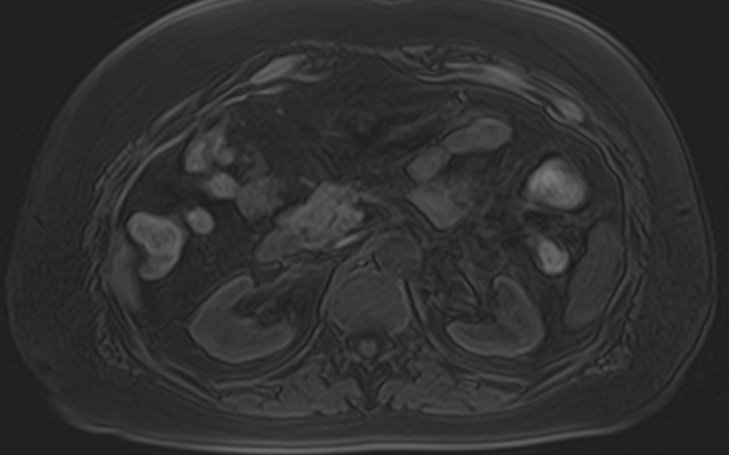

Магнитно-резонансная томография брюшной полости является наиболее информативной безопасной и эффективной методикой обследования внутренних органов. Метод позволяет проводить дифференциальную диагностику в сложных клинических случаях. Особенно это важно при противоречивых и неоднозначных данных, полученных при проведении УЗИ, рентгенографии, КТ или других обследованиях.

Методика МРТ основана на применении внешнего магнитного поля и отличается точностью и достоверностью полученных данных. Отсутствие вредного рентгеновского излучения делает процедуру безопасной и позволяет при необходимости проводить томографию несколько раз в течение короткого периода времени. Это бывает важно, например, для оценки динамики состояния патологических изменений в органах на фоне лечения.

Для расширения возможностей диагностики, при необходимости уточнения характера патологических изменений, в случае подозрения на опухолевый процесс, дополнительно применяется контрастное усиление.

Для этого в вену вводится контрастный препарат, содержащий металл гадолиний (Магневист, Гадовист, Омнискан и др). Степень и характер накопления контрастного препарата в органах и тканях позволяет различать патологические процессы. Это дает возможность, в частности, диагностировать патологические очаги минимальных размеров, что бывает особенно важно в ранней диагностике опухолей.

В клинике «Доступная медицина» МР томография проводится на новейшем высокопольном томографе экспертного класса TOSHIBA VANTAGE TITAN 1,5 Тесла. Высокая индукция магнитного поля обеспечивает повышенную четкость изображений при проведении обзорной МРТ брюшной полости, что гарантирует точность и эффективность диагностики заболеваний печени, желчного пузыря, поджелудочной железы и селезенки. Аппарат послойно сканирует исследуемую область с шагом от 1 мм в различных плоскостях, затем трансформирует результаты в трехмерные изображения превосходного качества. Для уточнения характера патологических изменений одного из органов назначается прицельная МР томография данного органа.